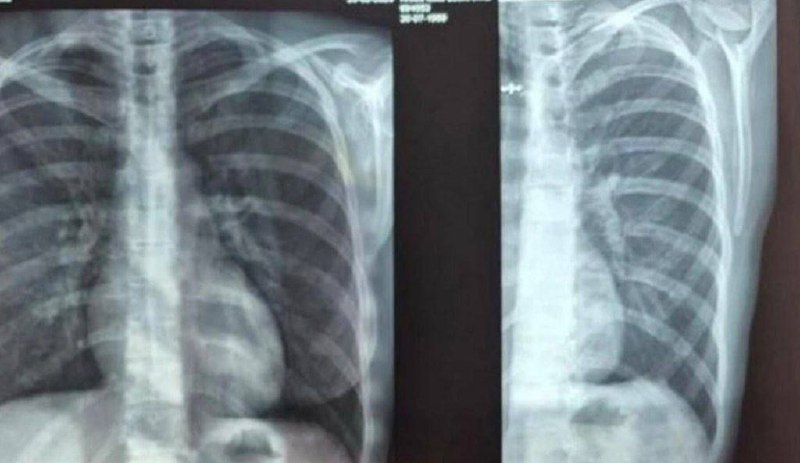

Жительница Екатеринбурга получила серьезную травму во время отдыха в загородном отеле